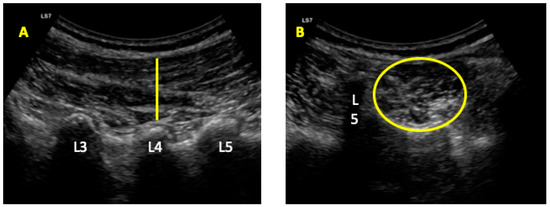

Ultrasonography was developed with a LogiQ ultrasound system (GE, Healthcare, UK), with a 4–13 MHz linear transducer (38-mm footprint) for the anterior abdominal wall muscles and with a 2–5.5 MHz convex transducer (38-mm footprint) for the multifidus evaluations. All the evaluations were developed by the same therapist (P.M.L.), with 3 years of experience in ultrasound imaging of the musculoskeletal field. All the images for the anterior abdominal muscles were taken in supine position. The images of the EO, IO, and TrAb muscles was developed by placing the transductor in the mid-axillary line, between the subcostal line and the iliac crest [9] (Figure 1A). For the RA muscle examination, the transducer was placed aligned with the umbilicus, and just under the umbilicus for the IRD evaluation (Figure 1B). Muscle thickness was considered as the distance between the edges of each muscle and IRD was described as the distance between the both RA muscles [9]. For the multifidus muscles examinations patients were placed lying in prone position at rest and during a maximal isometric contraction with the ipsilateral extended lower limb for 5 s. Following the Wallwork et al. [36] guidelines, the transducer locations were identified by palpations of L4–L5 spinous as the reference points. The thickness of the multifidus muscles was considered as the tip of the target zigapophyseal L4–L5 joint to the inside edge of the superior border of the multifidus muscle [36] (Figure 2A). According to Huang et al. [37], the CSA of the multifidus muscle was recorded with the transducer placed on the skin 25-mm distal from the spinous process of L5 and vertical to the spine (Figure 2B).

Figure 2. Ultrasound imaging for the multifidus thickness (A) and cross-sectional area (CSA) (B).